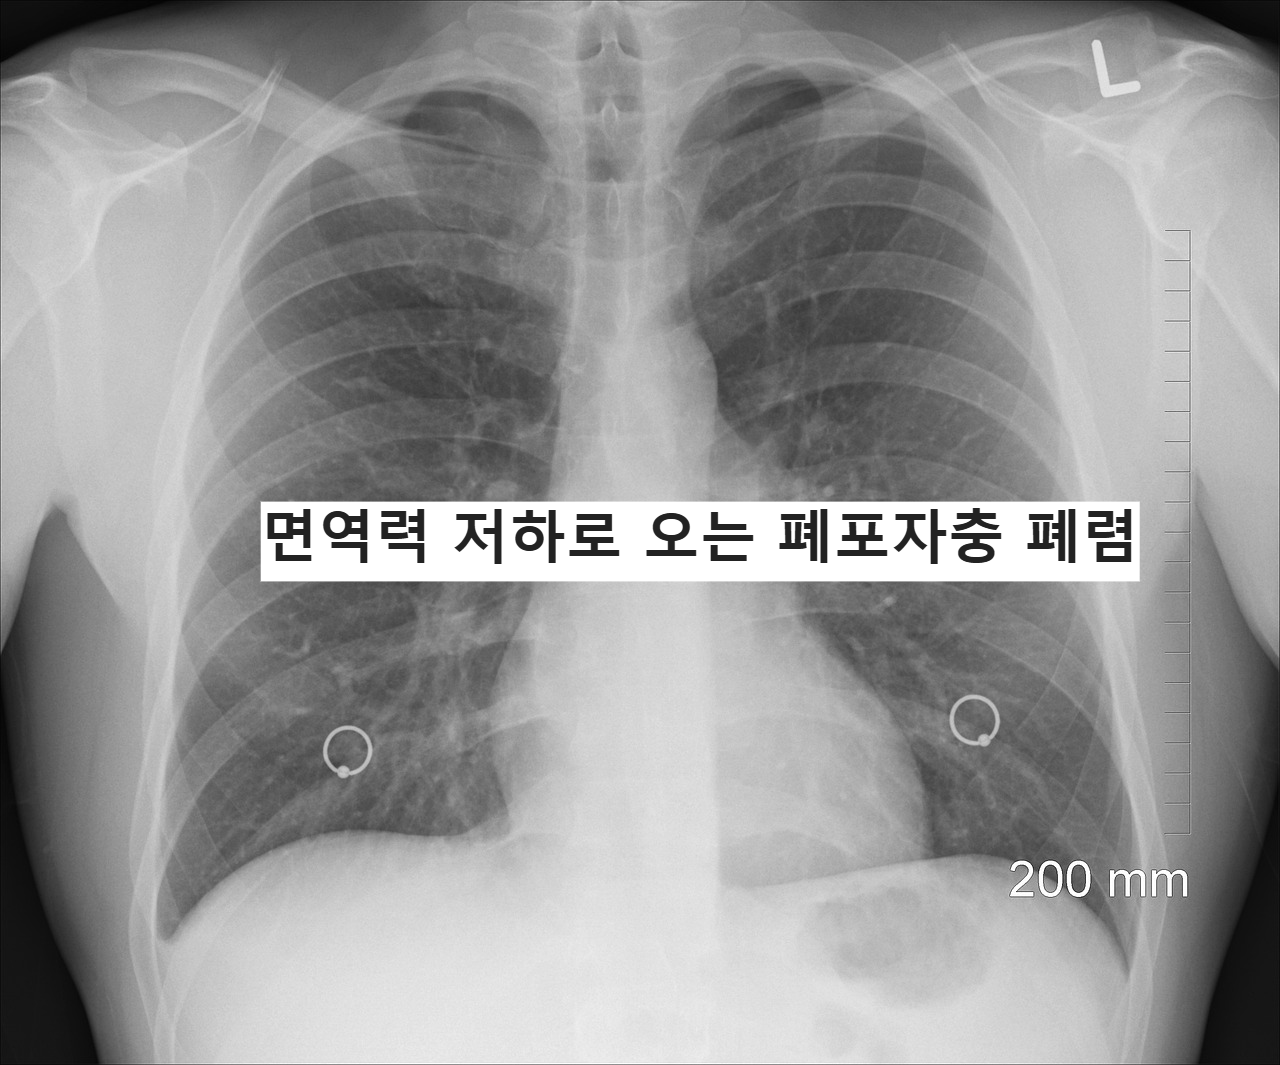

폐포자충폐렴은

일반적인 폐렴과

영상 소견이 다르게 나타나는 경우가 많다.

- 흉부 영상 검사

- 산소 포화도 확인

- 필요 시 추가 검사

증상과 위험 인자를 함께 고려해

진단이 이루어진다.

무엇보다 중요한 건

의심 자체를 놓치지 않는 것이다.